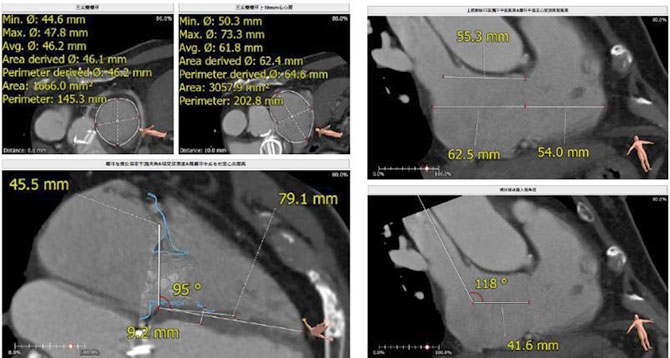

据悉,接受本次手术的患者是一位72岁老年男性,因“反复活动后气促1年,下肢水肿4个月”就诊。术前超声提示:重度三尖瓣关闭不全,三尖瓣收缩期位移(TAPSE)14mm,主动脉瓣、二尖瓣机械瓣功能良好。术前CT评估(图1):三尖瓣瓣环(周长换算)直径为46.2mm;入路血管无严重迂曲、钙化。

图1 术前CT评估结果